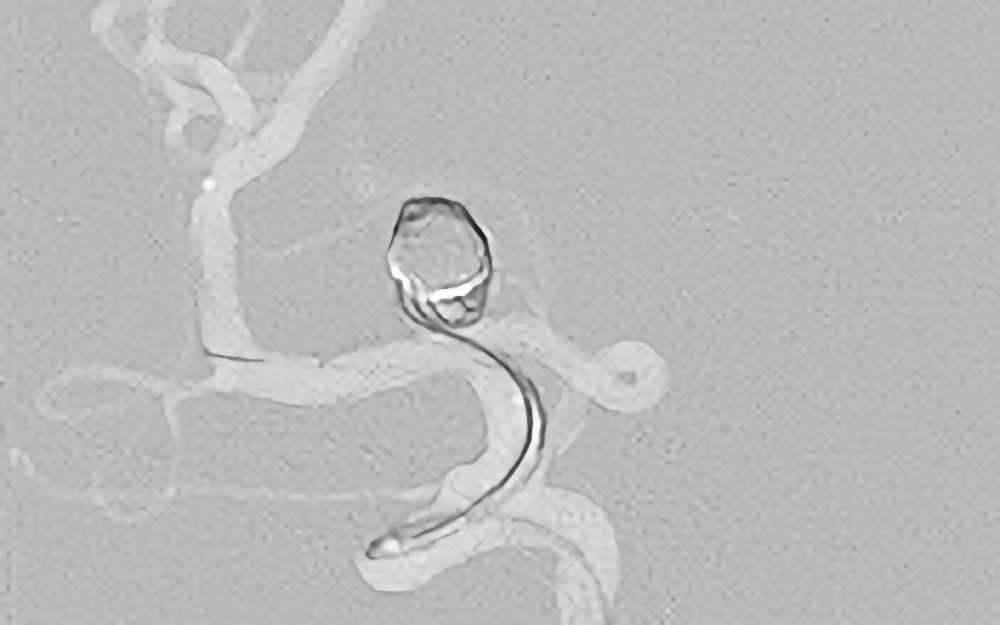

No.1617 手術後